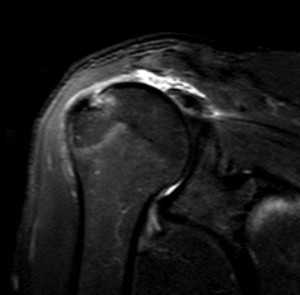

Разрыв вращательной манжеты - также характерное повреждение области плеча - может быть связан как с травмой, так и дегенеративными процессами. Разрывы вращательной манжеты бывают полные и неполные. Кроме того, по МРТ плечевого сустава выделяют 3 градации, в основе которых лежит не только изменение сигнала на Т2-зависимых томограммах, но и морфологические изменения сухожилия.

МРТ. Корональная Т2-зависимая томограмма с подавлением сигнала от жира. Полный разрыв сухожилия надостной мышцы.

При МРТ плечевого сустава косвенным признаком разрыва вращательной манжеты служит высокий сигнал на Т2-взвешенных от поверхности сустава до субакромиальной (субдельтовидной) сумки. Частичные разрывы чаще всего по передней поверхности сухожилия м.supraspinatus, реже примыкая к большой бугристости или сухожилия м. infraspinatus.

МРТ плечевого сустава. Т2-взвешенная корональная МРТ. Субакромиальное скопление жидкости - косвенный признак разрыва вращательной манжеты.

МРТ плечевого сустава. Т1-взвешенная корональная МРТ. Частичный разрыв вращательной манжеты.

МРТ плечевого сустава. Т2-взвешенная корональная МРТ. Передний разрыв вращательной манжеты